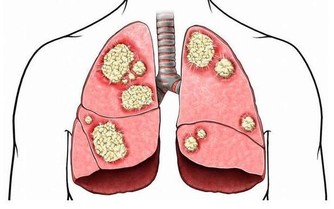

類型2/進食方式: 進食速度過快,或是在用餐過程中不斷說話,都可能導致吞嚥時,吸入大量的氣體,一旦累積到一定的量,便會以打嗝或放屁等方式排出。 類型3/腸道狀態: 正常人的腸道中或存有大量的細菌,來幫助人體維持消化功能的運作,可是,當身體狀態不佳、飲食長期不均衡時,腸胃道中的好壞菌比例便會失去平衡,使容易產氣的壞菌大幅增加,自然就會產生頻繁排氣的症狀。 類型4/腫瘤阻塞: 此外,大腸癌患者因腫瘤組織堵塞部分腸道,影響腸道蠕動造成積氣,也是導致「連環屁」、放屁次數大幅提升的原因之一。不過,值得注意的是,腫瘤要長到一定的大小,需要很長的一段時間;因此,此類症狀多出現於大腸癌後期的患者身上。 常放臭屁,是大腸癌前兆?醫:傳言不可信! 有鑒於此,「常放臭屁,恐是大腸癌前兆」的謠傳,其實並不完全正確,陳樞鴻醫師指出,除了屁臭不臭不是重點外,更不是大腸癌的「前兆」,反倒是大腸癌末期的病友較可能發生。

且頻頻放屁的症狀,也並非是所有腸癌患者都會出現。人體的腸道結構,主要除了居中的橫結腸外,又可區分為右大腸(升結腸、盲腸)、左大腸(降結腸、乙狀結腸、直腸)兩區塊。其中,右大腸(升結腸、盲腸)因彈性較佳,因此一旦癌細胞從此而生,往往患者發現時,腫瘤已變得相當大,且症狀上多以貧血較為常見。 至於放屁症狀,則較容易發生於,腫瘤組織位於後段左大腸(降結腸、乙狀結腸、直腸)部位的癌友身上。特別是大腸直腸癌者,由於直腸較接近肛門、管腔小,即便腫瘤不大也容易發生阻塞,因此引起放屁頻頻、腹痛、腹脹、便祕等症狀的機率自然較高,也較易有血便問題,發現率也較前者來的高。 【醫師小叮嚀】: 陳樞鴻醫師提醒,想要防範大腸癌上身,民眾應養成良好、規律的飲食及運動習慣,盡可能維持正常作息;至於50歲以上的人,更要定期接受國民健康署建議的「糞便檢測」,早期發現、早期治療,自然健康有保障!